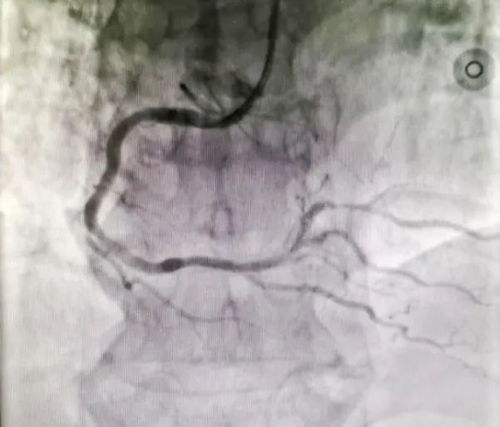

胸痛二線立即啟動導(dǎo)管室,與家屬溝通病情,并做好術(shù)前的一切準(zhǔn)備工作。在家屬知情同意后,立即給予冠脈造影檢查。

RCA遠(yuǎn)段后三叉前局限性狹窄約95%

情況緊急,必須盡快開通血管,改善心肌血供,減輕患者痛苦。

鄭州陽城醫(yī)院胸痛中心在春節(jié)假期連續(xù)兩天成功救治兩名急性心;颊

我院胸痛中心手術(shù)團隊嫻熟緊密地配合,在10分鐘內(nèi)成功于右冠遠(yuǎn)段植入1枚支架,讓病變殘余狹窄消失,冠脈血流恢復(fù)正常,患者生命體征平穩(wěn),送回病房進一步診治。